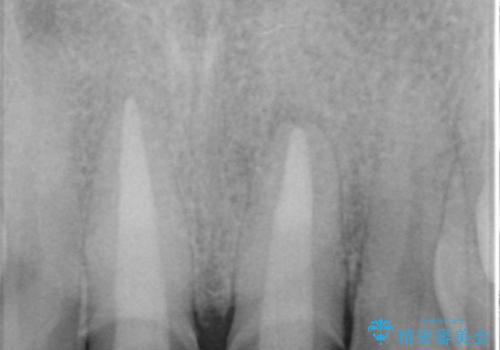

X線写真より、根尖部に透過像が認められ根管治療・ファイバーコア築盛・セラミッククラウンの作製が必要な状態です。

X線検査や歯周組織検査などを行い適切な治療を行うことで良好な結果を得ることができます。